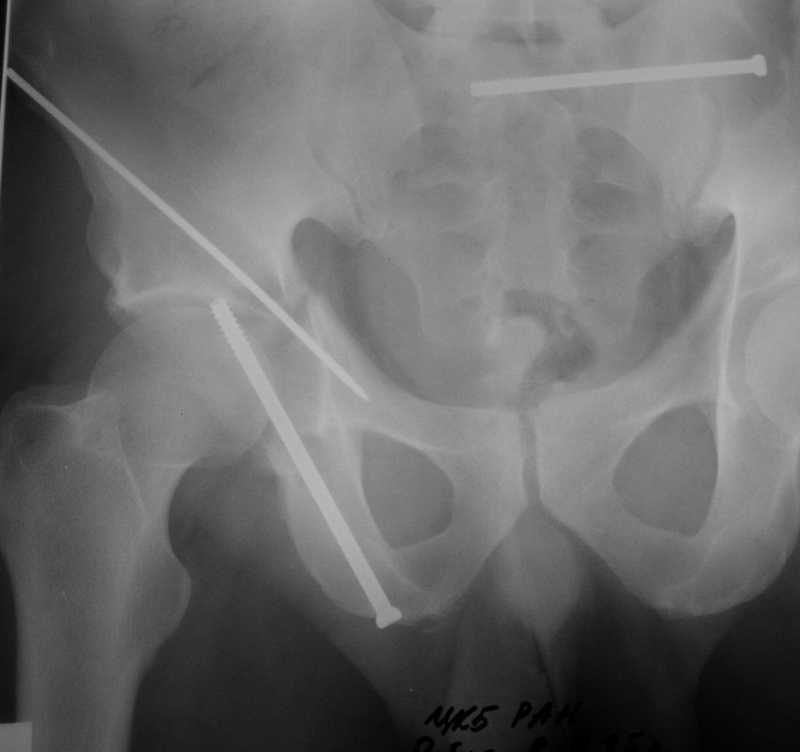

Yordan! In this case position of bone fragments is quite good. We

prefer to use miniinvasive technique. We fix posterior column by can. screw and put 3mm pin with distal thread to the anterior column. Next day after the surgery he may start walking with crutches. 3 month after the surgery we remove the pin. In cases of maleolar fractures we use

angle stable plates to lat. mal. and pins or screws and if syndesmosis is intact - full loading is not forbidden.

Sending exampl pict.